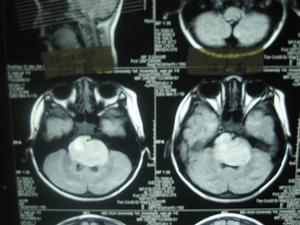

(三)仔細進行神經系統與軀體檢查:有無可疑的陽性體徵,各項輔助檢查(如頭顱平片、腦電圖、顱腦CT檢查,無疑有助於腦瘤診斷,但任何單項檢查均有一定的陰性率,故須結合病史和臨床表現全面考慮,必要時行顱腦核磁共振檢查。成人腦部轉移癌以來自肺、肝、腎、胃者居多,進行相應的輔助檢查。

4.輔助檢查見顱腦腫瘤有關腦腫瘤部分。